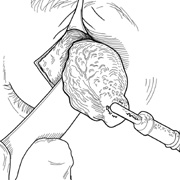

Fig. 9. A,B. Coronal and axial CT images of a large intraconal neoplasm. C. Because it was felt to represent a well-encapsulated cavernous hemangioma, this lesion was a candidate for removal via an eyelid crease orbitotomy without bone removal. The eyelid crease incision marked. D. Incision made with scalpel. E. Orbicularis muscle is tented up and incised to expose the underlying septum. F. Dissection of a skin-muscle flap deep to orbicularis exposes the orbital septum and superior orbital bony rim. G. Cutting cautery is used to incise periosteum along the superior and lateral rims; finger palpation of the bone helps to direct this incision. H. Periorbita is elevated along the mesial surface of the lateral orbital rim in order to expose the deep orbital tissues. I. The cavernous hemangioma is visualized in the wound. Retraction is provided by one or more malleable retractors. J. Cryoprobe is affixed to the hemangioma to facilitate manipulation of the lesion. K. Large cavernous hemangioma after removal through the eyelid crease incision which was accomplished without bone removal. L. Periorbita is reattached over the lateral rim. M. The eyelid crease incision is closed with a running suture.

CANTHOTOMY APPROACH